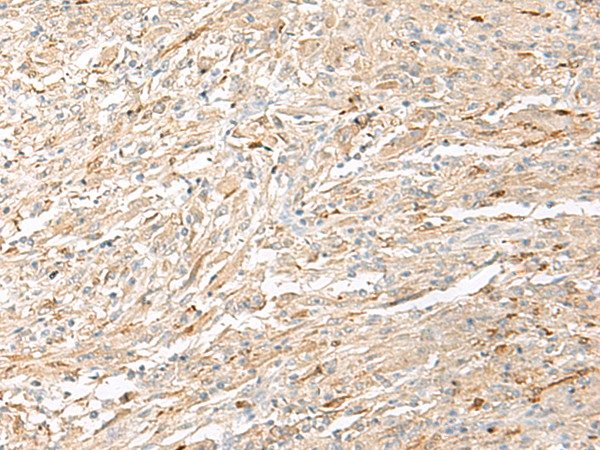

分类: 科研抗体货号: P06644别名: RAIG3; RAIG-3应用: IHC反应种属: Human, Mouse